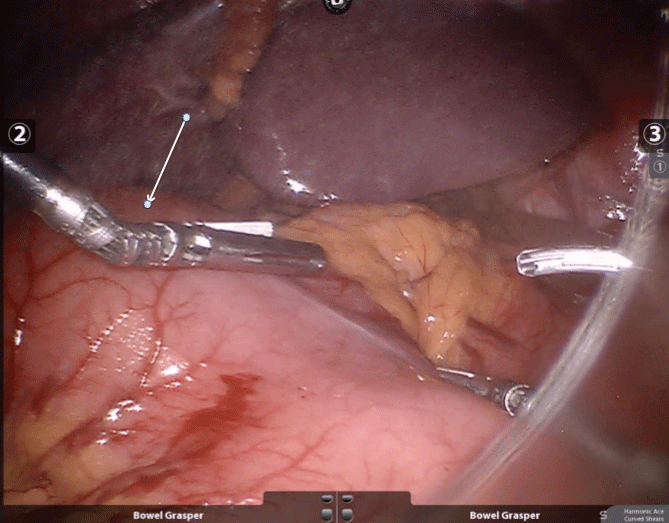

The patient is a 29-year-old man with no significant medical or surgical history who presented with 2 months of nausea, emesis, and 20 pounds of unintentional weight loss. On initial presentation, he was afebrile with normal vital signs. His abdomen was soft, non-distended and non-tender. Initial laboratory parameters revealed a hypokalemic, hypochloremic metabolic alkalosis consistent with a clinical picture of gastric outlet obstruction. Computed Tomography (CT) of the abdomen and pelvis (Figure 1) revealed a 3.5 × 4.9 cm cyst proximal to the pylorus, suggestive of a gastric duplication cyst, causing a gastric outlet obstruction. Endoscopy demonstrated a large pre-pyloric mass without noted mucosal abnormality or luminal connection, likely responsible for the gastric outlet obstruction (Figure 2). Antral biopsies revealed mild chronic inflammation and mild foveolar hyperplastic changes. Given gastric outlet obstruction as well as imaging suggestive of a duplication cyst, the patient was taken to the operating room and underwent robotic assisted laparoscopic distal gastrectomy with Billroth 2 gastrojejunostomy for a suspected gastric duplication cyst (Figure 3). Final pathology revealed features consistent with a gastric duplication cyst (5.2 × 4.0 × 4.0 cm) not communicating with the gastric lumen (Figure 4).

Figure 3: Intraoperative photograph demonstrating the external appearance of the gastric duplication cyst (arrow).